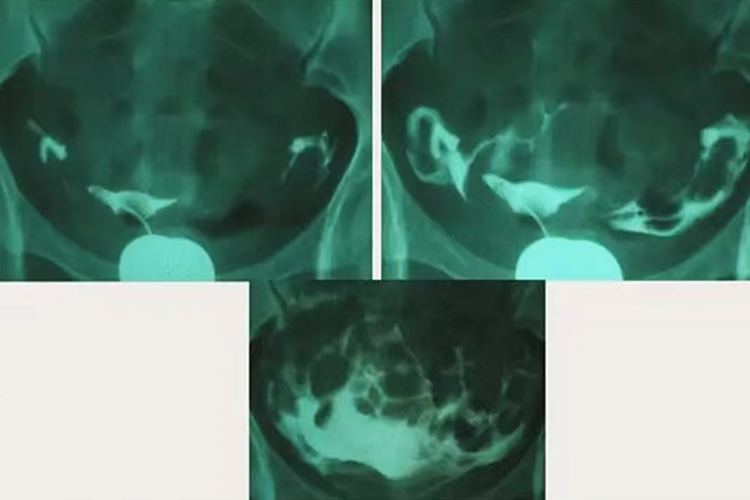

正常子宫、输卵管进行传统的子宫输卵管造影时,可见宫腔呈倒三角形,双侧输卵管显影,形态柔软,24小时后摄片见盆腔内散在造影剂分布,超声下子宫输卵管造影时可实时监控,见造影剂充盈宫腔,并从双侧输卵管流出并包绕同侧卵巢。